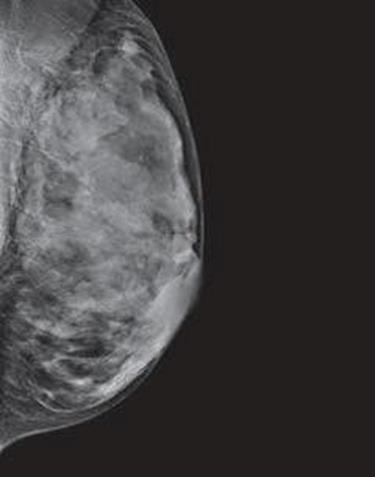

Dense breast tissue, as seen on a mammogram, has more fibrous connective tissue and glandular tissue, and less fatty tissue. It is often inherited, but menopausal hormone therapy, and low body mass index are factors associated with breast density. Dense breast tissue is a risk factor for breast cancer, and a radiologist can tell if a woman has dense breasts.

A mammogram uses X-rays (ionizing radiation) to create images of the inside of the breast to check for cancer and other conditions. It can be used for screening to detect cancer, for instance, before there’s a lump in the breast, or to assist in the diagnosis of cancer. Radiologists use mammograms to interpret, and classify breast density into four categories.